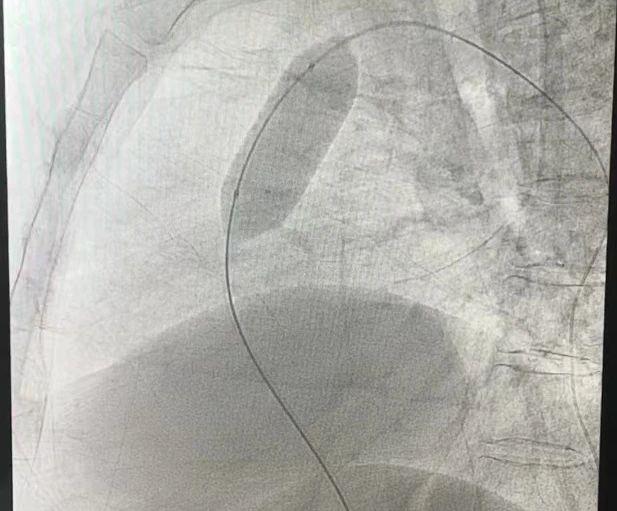

球囊扩张肺动脉瓣